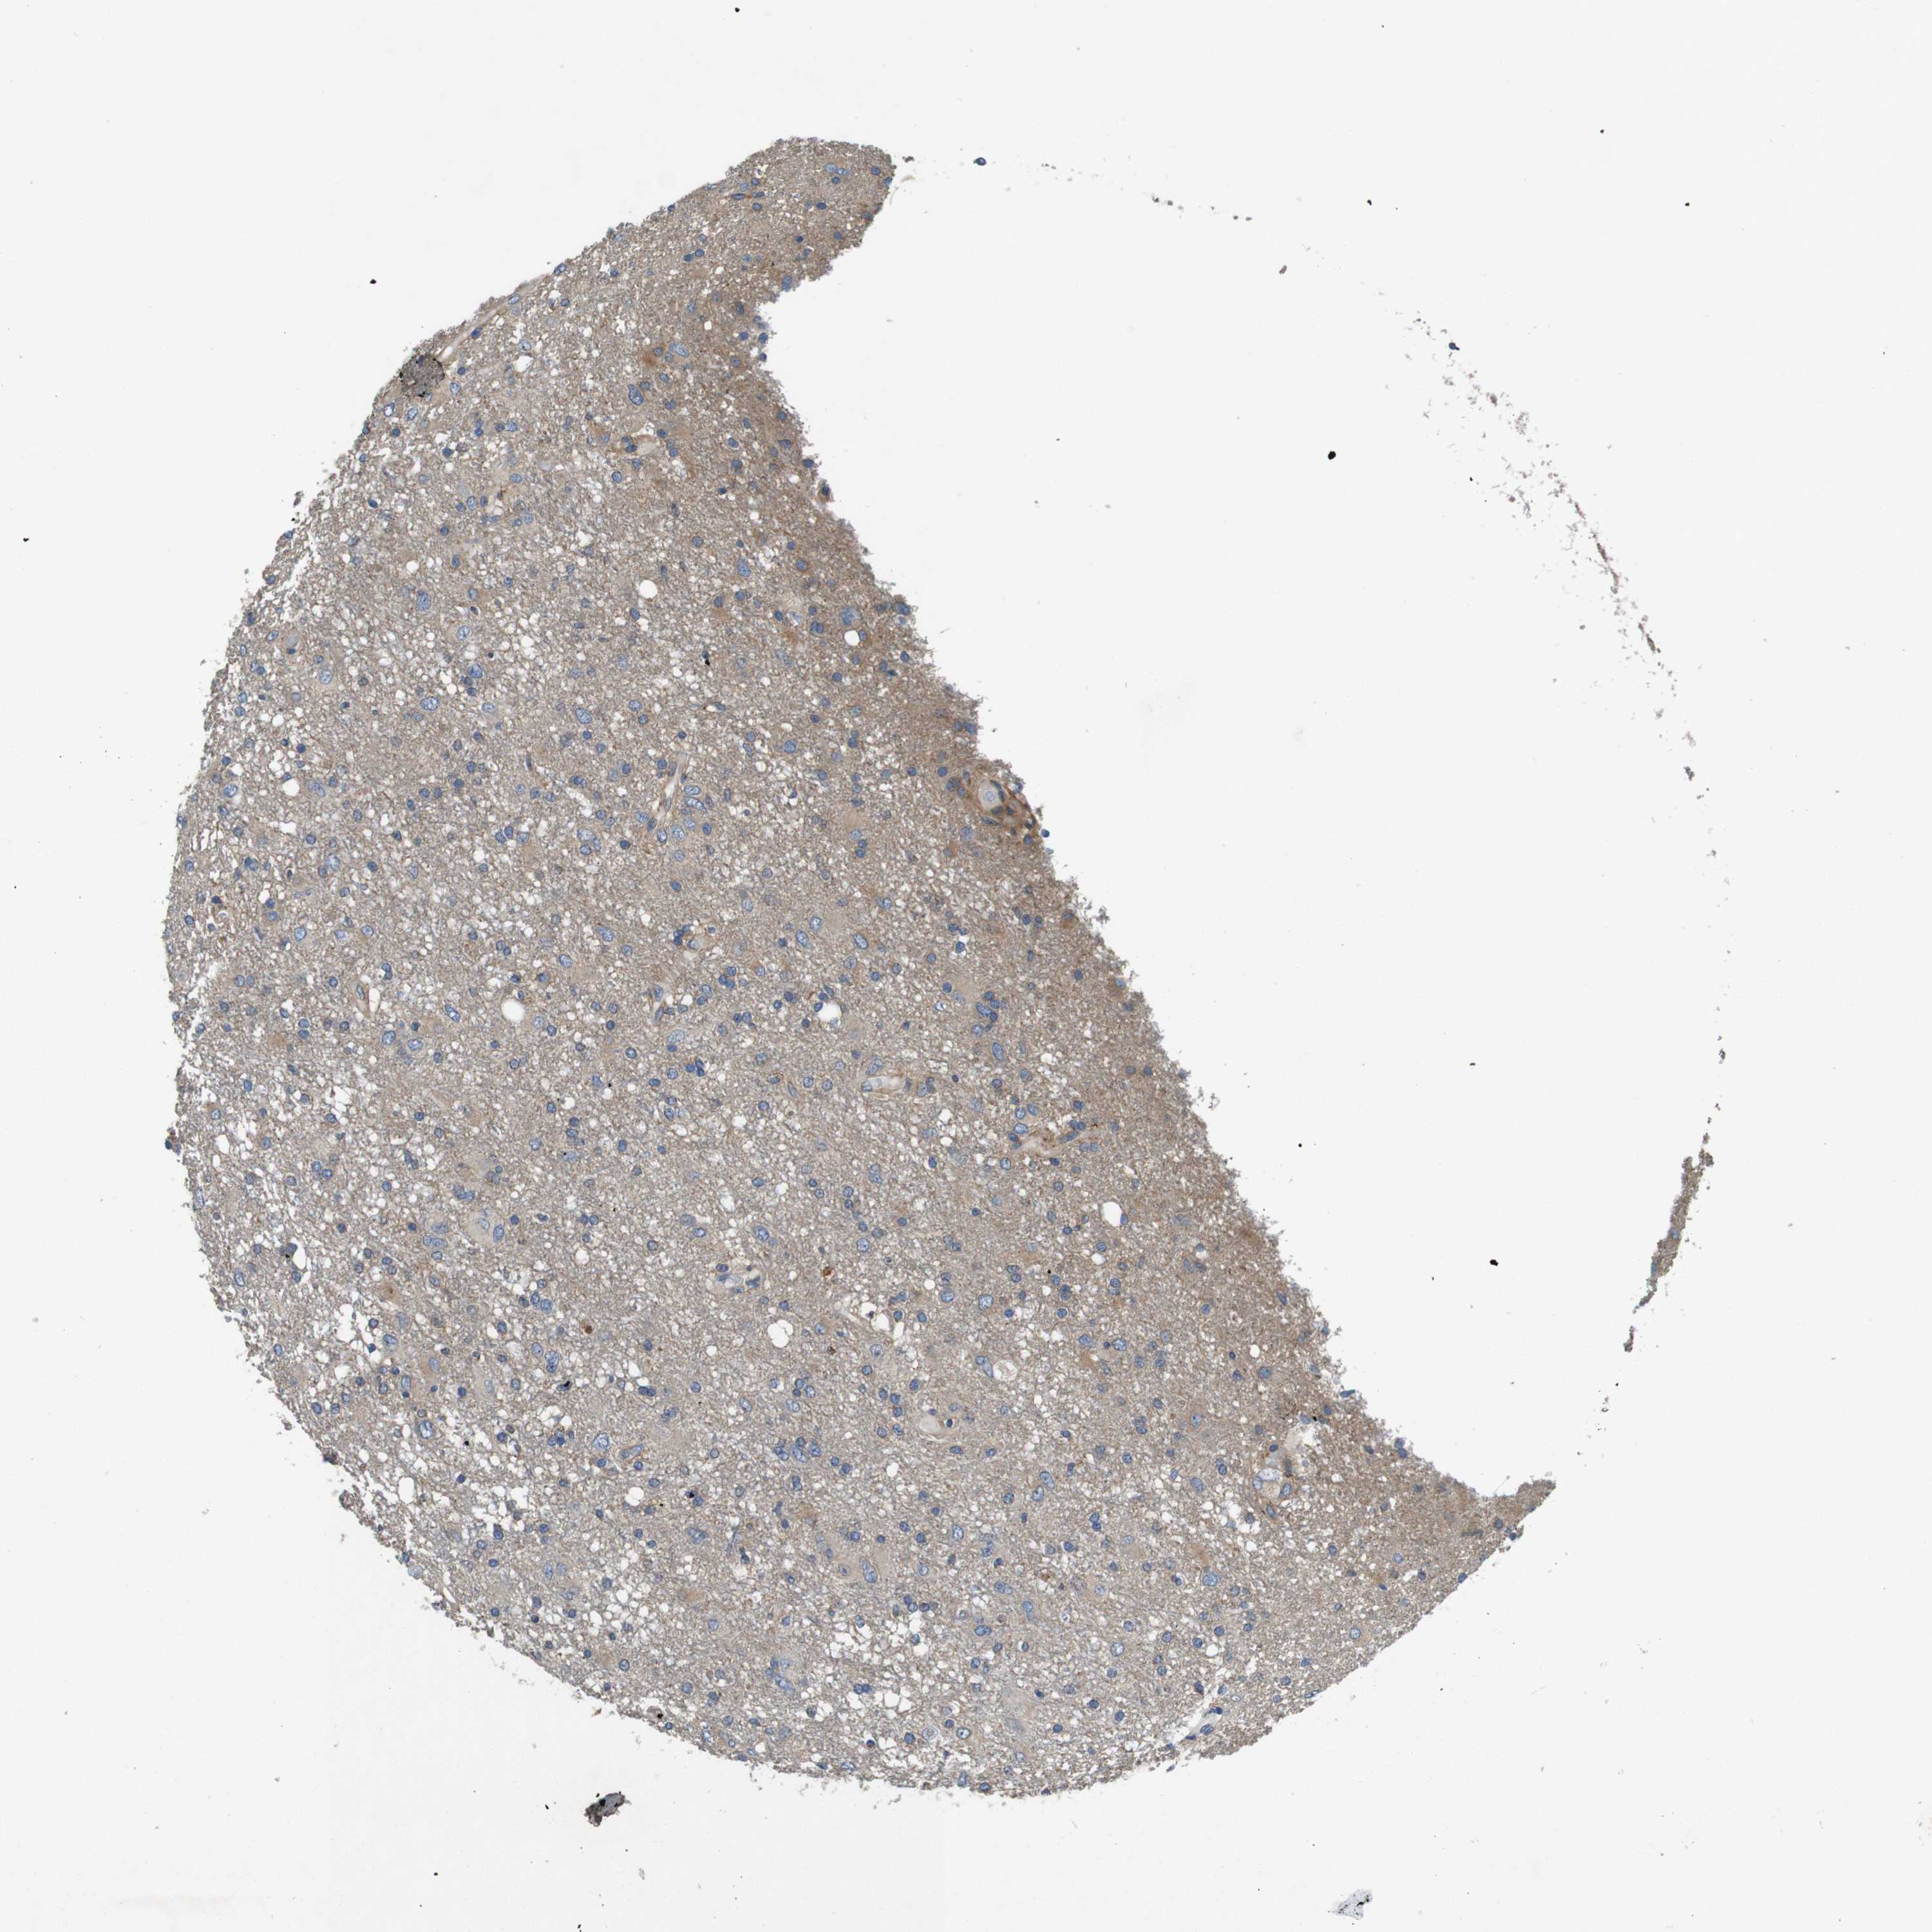

GLIOMA - Protein expressioni

A mouse-over function shows sample information and annotation data. Click on an image to view it in a full screen mode. Samples can be filtered based on level of antibody staining by selecting one or several of the following categories: high, medium, low and not detected. The assay and annotation is described here.

Note that samples used for immunohistochemistry by the Human Protein Atlas do not correspond to samples in the TCGA dataset.

Antibody stainingi

Antibody staining in the annotated cell types in the current human tissue is reported as not detected, low, medium, or high, based on conventional immunohistochemistry profiling in selected tissues. This score is based on the combination of the staining intensity and fraction of stained cells.

Each image is clickable and will lead to virtual microscopy that enables deeper exploration of all samples and also displays staining intensity scores, fraction scores and subcellular localization as well as patient and tissue information for each sample.

Antibody HPA034635

Antibody HPA069977

Antibody HPA071875

Antibody CAB009108

Staining

High

Medium

Low

Not detected

Intensity

Strong

Moderate

Weak

Negative

Quantity

>75%

75%-25%

<25%

None

Location

Nuclear

Cytoplasmic/membranous

Cytoplasmic/membranous,nuclear

Glioma, malignant, Low grade

Glioma, malignant, High grade